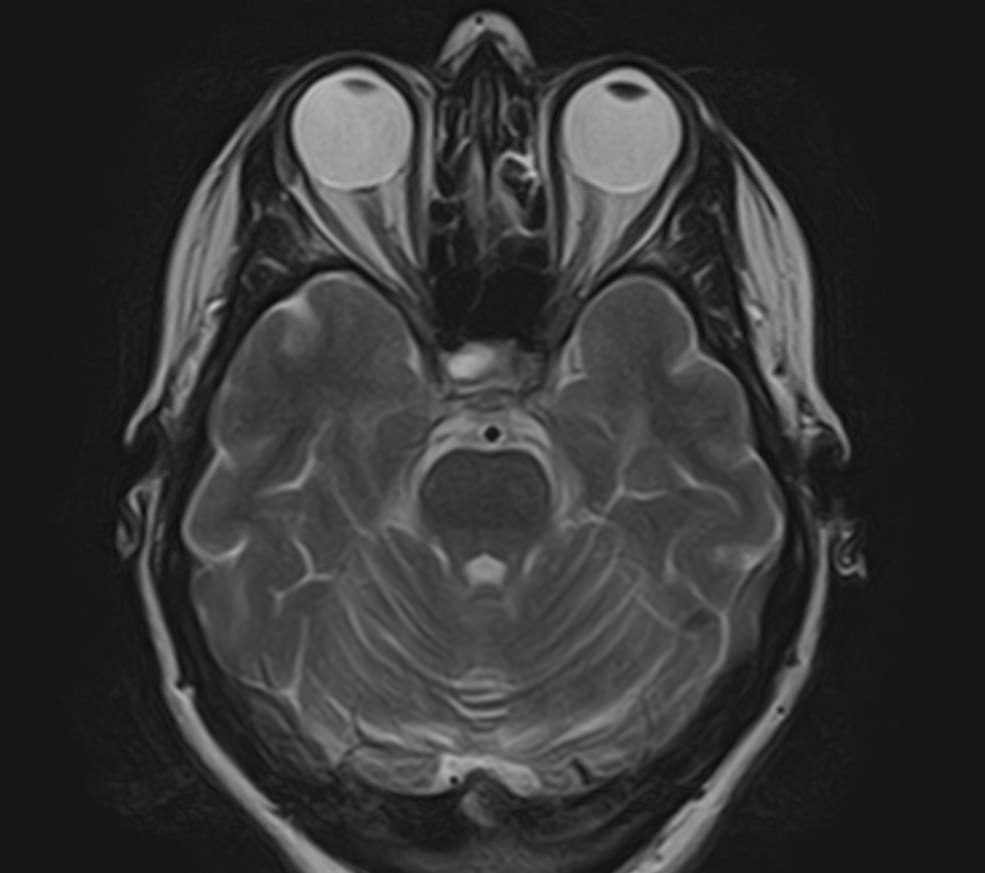

МРТ головного мозга позволяет оценить состояние всех структур головного мозга, однако для выявления патологии гипофиза назначается дополнительно МРТ гипофиза с прицельным осмотром области турецкого седла. Это два разных обследования, каждое из которых имеет свой протокол сканирования. Причем в подавляющем большинстве случаев МРТ гипофиза проводится с контрастным усилением, так как без этого данное исследование малоинформативно.

Опухоли гипофиза являются достаточно часто встречающейся патологией, особенно у людей молодого и среднего возраста. При этом выявляются как злокачественные, так и доброкачественные новообразования. В большинстве случаев обнаруживаются аденомы гипофиза (доброкачественные образования). При проведении стандартной МРТ головного мозга можно выявить достаточно большие опухоли гипофиза (от 1 см), а для выявления опухолевых образований меньших размеров (микроаденом) требуется МРТ гипофиза с контрастным усилением.

Метод позволяет создавать детализированные изображения всех структур головного мозга, в том числе области турецкого седла, и по праву считается лучшим способом диагностики любых объемных образований гипофиза. С помощью МРТ головного мозга и гипофиза можно выявить макроаденомы и большинство микроаденом (размером до 3мм).